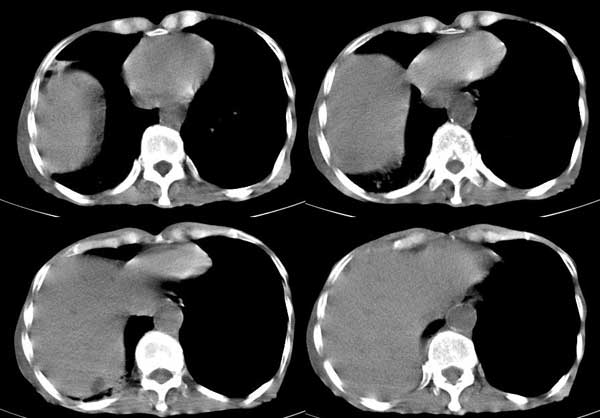

患者男,81岁,咳喘10余年,继往结核病史,发现胸部体表肿物(具体时间不详)就诊

右侧胸廓塌陷。右前上外侧胸壁软组织肿块,其内见有低密度影,肋骨呈溶骨性表现。右肺上叶见大量的间质纤维化表现。右侧膈肌上抬。

患者男,81岁,咳喘10余年,继往结核病史,发现胸部体表肿物

考虑:1、继发性结核,右结核性胸膜炎伴胸壁结核性感染

2、右侧胸壁恶性肿瘤。

患者男,81岁,咳喘10余年,继往结核病史,发现胸部体表肿物。

考虑:1 右侧胸壁恶性肿瘤(多考虑:胸膜间皮瘤)。

2 继发性结核,右结核性胸膜炎伴胸壁结核性感染。

考虑右侧胸壁恶性肿瘤伴右肺癌性淋巴管炎 (肺上沟瘤常有神经方面的症状,结核如此严重无明显结核中毒症状也很少见)